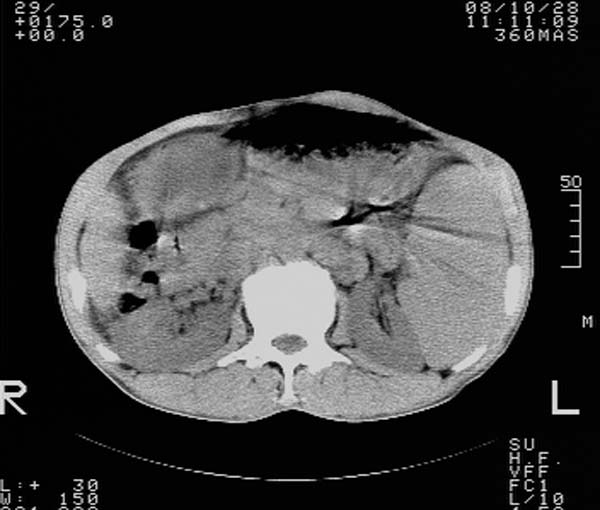

m,65y。半年前发现颈小结节,逐渐增多增大,现双侧耳后、颌下及颈部表浅淋巴肿大。胸片示双肺门增大。外院曾穿刺诊断为淋巴结核。在我科作胸腹部ct,我们觉得外院病检有误。现将图像上传请战友讨论。

纵隔内及腹膜后广泛淋巴结肿大,脾大,肝内似可见低密度影,结合病史半年前发现颈小结节,逐渐增多增大,现双侧耳后、颌下及颈部表浅淋巴肿大。考虑淋巴瘤。

我们也是首先考虑淋巴瘤。只是外院病检报告是结核。让人迷惑。肝左叶多发低密度占位,没增强不好定论。

纵隔,双肺门腹膜后多发淋巴结重大,非融合,肝脾轻度肿大,双肺野弥漫性小结节;考虑淋巴瘤,结节病可能性

纵隔内,双肺门、腋窝及腹膜后多发肿大淋巴结影,肺内小结节影,肝脾体积增大,支持淋巴瘤。肝内多发低密度影,考虑小囊肿。

纵隔内,双肺门、腹膜后多发肿大淋巴结影及颈部淋巴结肿大,肝脾体积大.结合临床,淋巴瘤可能性大。